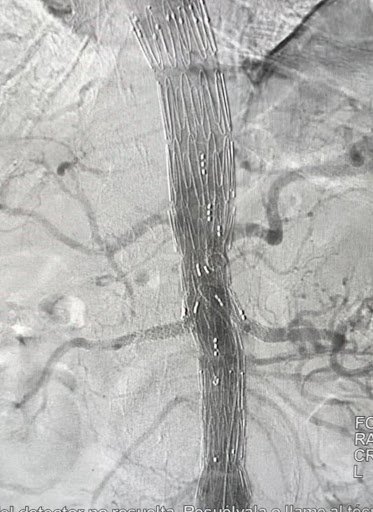

• Reconstrucción venosa profunda Tratamiento especializado de obstrucciones iliofemorales, secuelas postrombóticas y enfermedad venosa compleja, orientado a restaurar función y mejorar calidad de vida.

Reconstrucción venosa profunda

Tratamiento especializado de obstrucciones iliofemorales, secuelas postrombóticas y enfermedad venosa compleja, orientado a restaurar función y mejorar calidad de vida.